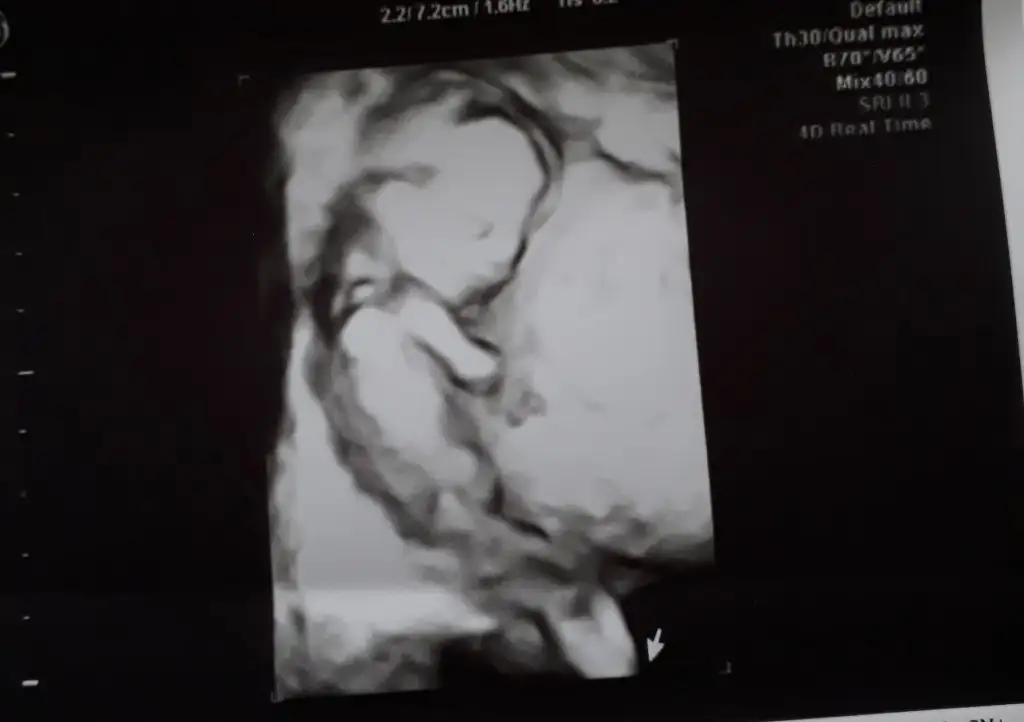

Kızlar bence bu tamamen şans kız istersen erkek erkek istersen kız oluyor benim de oğluşum olacakmış

Hayirli uğurlu olsun canım oğluşun . Bende ultra pikten 1 2 saat sonra iliski oldu kızım olacak. Bende erkek diye planlamistim. Hayırlisi buymus. Hayirli evlat olurlar inşallah. Rabbim herkese gönlündekini nasip etsin

Ya vallahi bnde şaşırdım kız olması gerekirken erkek dedi şoka girdim😂😂😂